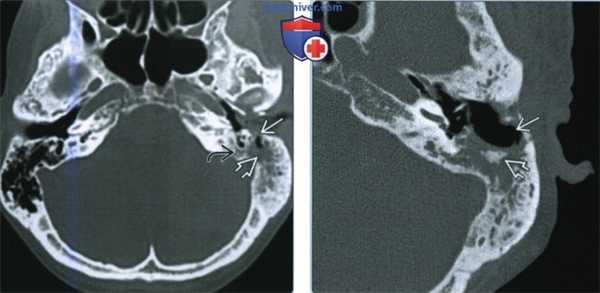

(Слева) При аксиальной КТ в коаном окне определяется патологическая мягкая ткань, заполняющая левый наружный слуховой канал (НСК) и ячейки сосцевидного отростка с явной деструкцией задней стенки ВСК и перегородок в сосцевидном отростке. Обратите внимание на смешанные склеротические и литические изменения костей - типичный вид височной кости при остеорадионекрозе.

(Справа) При аксиальной КТ в костном окне определяется радиационно-индуцированный некроз костного НСК и сливная деструкция ячеек сосцевидного отростка. Обратите внимание на «плавающий» костный секвестр. Все изменения указывают на тяжелый остеорадионекроз.